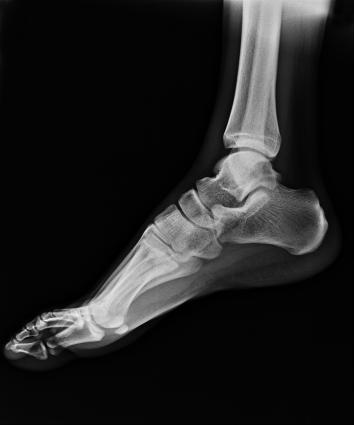

電動(dòng)旋轉(zhuǎn)內(nèi)平衡結(jié)構(gòu),可實(shí)現(xiàn)快捷擺位,滿(mǎn)足特殊體位的靜態(tài)與動(dòng)態(tài)檢查。